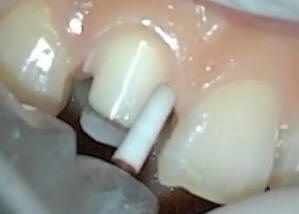

El tallado se continua

por vestibular y palatino |

Vista palatina del

tallado |